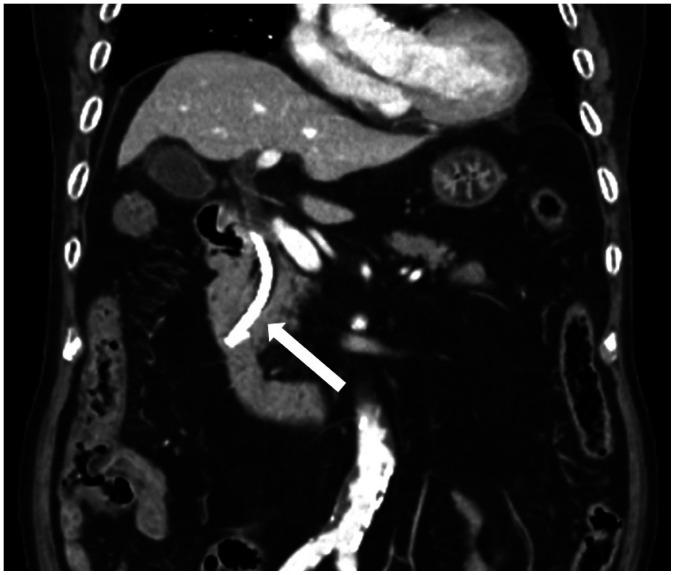

A variety of medical devices have evolved throughout the years. Commonly used devices have typical radiological appearances which are familiar to radiologists. However, some new devices, as well as devices that are not commonly used, may be missed or misinterpreted by radiologists. It is even more difficult to identify a certain medical device with limited clinical history. Therefore, accurate identification of medical devices is crucial to diagnose malposition and potential complications. In this article, we provide a pictorial review of medical devices of the abdomen and pelvis according to classifications that include gastrointestinal devices, hepatobiliary devices, genitourinary devices, and miscellaneous. We also comprehensively review the clinical and radiologic features of complications related to these medical devices.

多年来,各种各样的医疗设备不断发展。常用设备具有典型的放射学表现,放射科医生对此很熟悉。然而,一些新设备以及不常用的设备可能会被放射科医生遗漏或误判。在临床病史有限的情况下,识别某种医疗设备就更加困难。因此,准确识别医疗设备对于诊断位置异常和潜在并发症至关重要。在本文中,我们根据分类对腹部和骨盆的医疗设备进行了图片综述,分类包括胃肠道设备、肝胆设备、泌尿生殖系统设备以及其他设备。我们还全面回顾了与这些医疗设备相关并发症的临床和放射学特征。